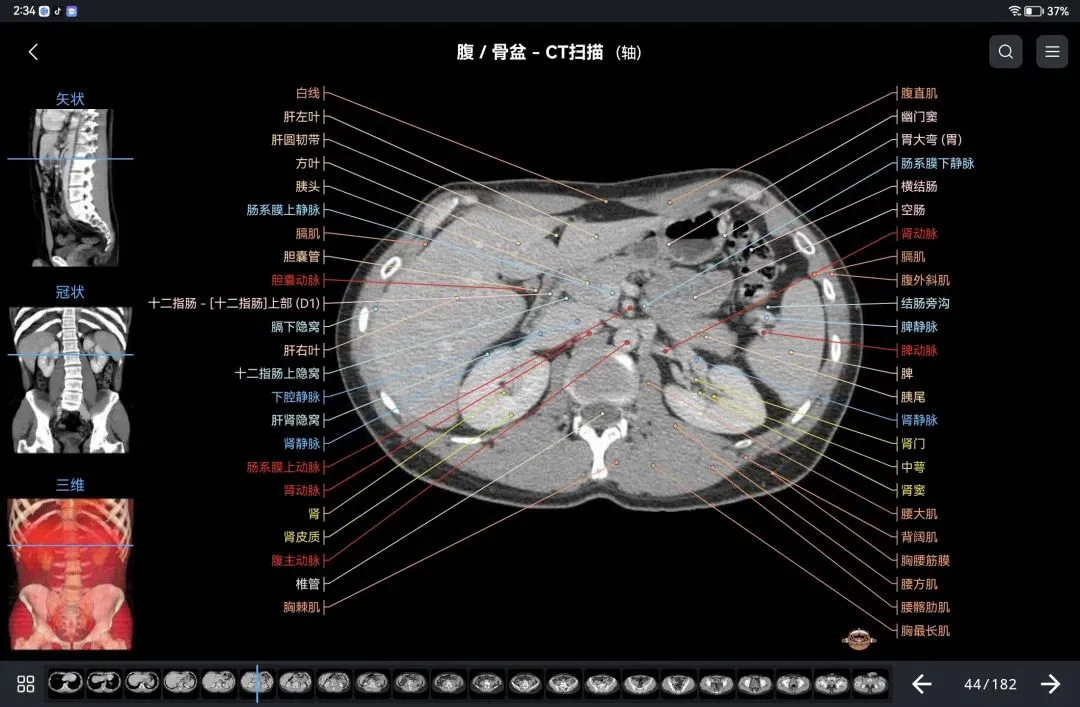

覆盖了X光、CT、MRI、断层大体解剖、核医学、介入造影、医学插图等多个模块,覆盖全身各个系统的影像解剖(正常解剖结构,无病例),其中的解剖结构高达87万个,结构标注超精细,超高清图像,历时两年研发设计完成✅。